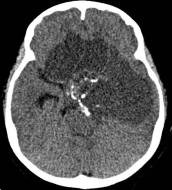

鉴于肿瘤体积超大,而且患儿间断出现意识障碍,直接作手术完全切除肿瘤的难度很大,为降低手术风险,所以我们采用先穿刺肿瘤囊减少肿瘤体积,降低颅压,二期手术争取完全切除肿瘤的策略。行肿瘤囊肿穿刺后,引流出约100多毫升囊液,肿瘤体积显著变小,见图3、图4。

图4.肿瘤囊穿刺手术后肿瘤体积减小

白色箭头示引流管